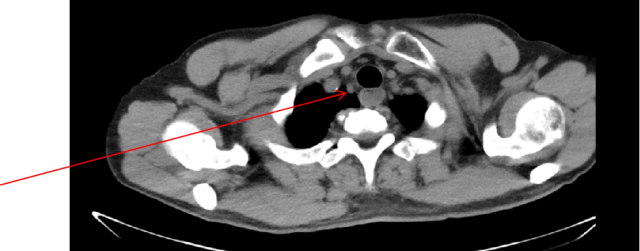

2025-01-10 :胸+全腹(含盆腔)CT 平扫:与(2024-09-13 CT)对比:双肺见多发结节灶,较大者位于右肺下叶内基底段胸膜下(Img 56/276),大小约 2.2×1.6cm,较前范围略缩小,余结节较前未见明显变化。双肺多发结节,右肺下叶内基底段结节较前略减小,余未见明显变化,建议密切随诊复查;食管下段周围肿大淋巴结,较前变化不著。转移灶缩小 PR。

2025-01-10